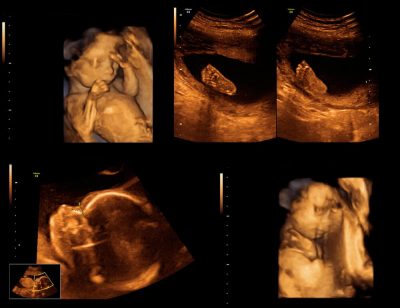

Bu gebelik haftaları arasında ultrasonografi ile bebeğin; ...

Bu haftalarda yapılan ultrasonografi ile bebeğin ; ...